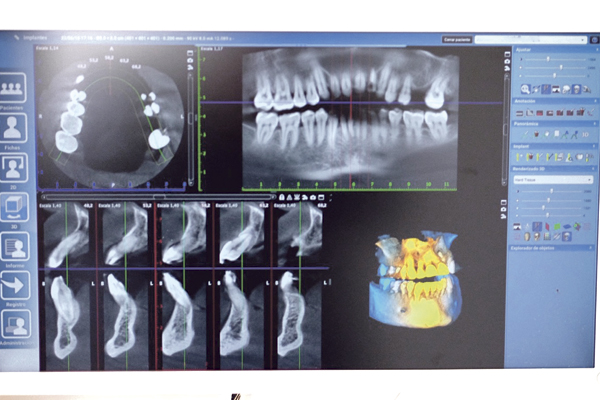

Consiste en la obtención de imágenes a través de la aplicación de rayos x que son recogidos por un sensor que diferencia la densidad de los diferentes tejidos en base a la diferente absorción por parte de estos de la aplicación de rayos, transmitiendo toda la información a un ordenador que reconstruye los diferentes planos de una toma de 360 grados en imágenes tridimensionales nítidas y con elevado contraste.

La versión dental de un TAC tradicional se denomina por sus siglas en inglés CBCT (Cone Beam Computed Tomography) o Tomografía Computerizada de haz cónico, y sus principales diferencias frente a un TAC tradicional es la forma de emisión de los rayos, (en forma de abanico el TAC y en forma de haz cónico el CBCT) y el nivel de radiación, un CBCT dental moderno equivale a 75 TACs, es decir un CBCT moderno emite un nivel inapreciable de radiación frente a un TAC tradicional.

El TAC dental tiene dos grandes ventajas respecto a la radiografía tradicional panorámica o radiografía 2D, primero ofrece una representación visual en tres dimensiones de las estructuras dentales muy precisa, pudiendo ver malposiciones o malformaciones dentales con un nivel de detalle imposible con una radiografía panorámica tradicional y segunda al ser en 3D permite ver zonas ocultas posteriores que no se ven en una radiografía tradicional.

EL TAC se compone del propio aparato emisor y captador de imagen, un potente ordenador que reconstruye las tomas de 360 grados en imágenes tridimensionales y un software asociado que permite gestionar y visualizar las imágenes tomadas. Hoy en día un TAC es una herramienta imprescindible y vital para un correcto diagnóstico dental y absolutamente necesaria en un dentista para algunos tratamientos como son cirugías, implantes, reendodoncias y ortodoncias invisibles.